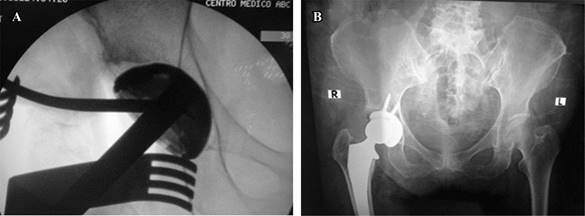

Intraoperative femoral or acetabulum fractures must be addressed. Femoral fractures could occur as with any other surgical approach for THA during stem insertion, and these injuries can be divided into two types: calcar or greater trochanter fractures. For the anterior approach, the reported rate ranges between 1.0 and 2.2% in multiple papers, with a little over half requiring fixation. Calcar fractures should be treated with cerclage and greater trochanter fractures with observation19,20 (Figure 5).

Figure 5: A) Calcar fracture during femoral stem insertion. (Pointed with the suction device). B) Fracture cerclage with Cables, postoperative anteroposterior (AP) pelvis X-ray.